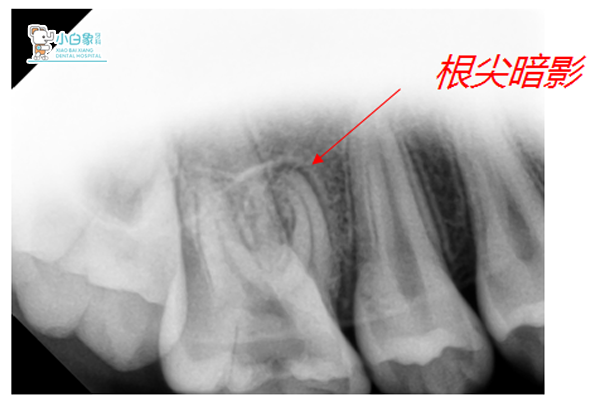

X线:16低密度影像达髓腔,近中根尖见低密度影像。

诊断:16慢性根尖周炎急性发作